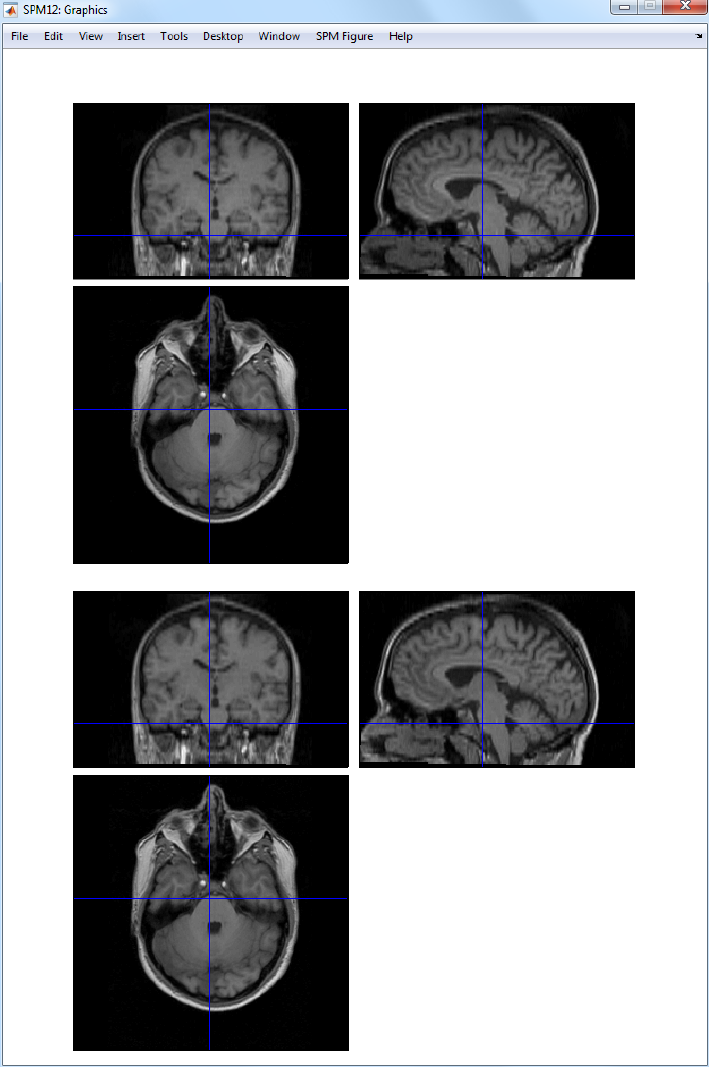

30.2.4 Normalise .....................................227

31.1.6 Normalise .....................................251

42.7.4 Application of Normalisation parameters to EPI data ............422